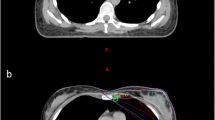

As shown in Fig. 1, exemplary for one patient, during T-DIBH, the heart, LMCA, and LADCA moved caudally compared with those during FB. Of note, the heart, LMCA, and LADCA moved farther caudally during A-DIBH than during T-DIBH. In other words, both DIBH techniques increased the distance between the heart and the breast CTV compared with FB. When A-DIBH and T-DIBH were examined separately, the heart moved farther away from the breast CTV during A-DIBH than during T-DIBH. In addition, the left lung volume increased during T-DIBH and A-DIBH compared with FB.

The relative spatial position relationships of the breast CTV (orange), left lung (blue), heart (red), LMCA (green), and LADCA (yellow) in a typical patient during FB (a), T-DIBH (b) and A-DIBH (c). A vertebral body T7 (blue) is contoured as a position marker in the shown case. During T-DIBH, due to expansion of the left lung (B), the heart, LMCA, and LADCA are moved caudally compared with during FB (a). During A-DIBH (c), the heart, LMCA, and LADCA are moved farther caudally than during T-DIBH (b). During T-DIBH (b) and A-DIBH (c), the breast CTV is moved cranioventrally compared with during FB (a) due to the expansion of the left lung